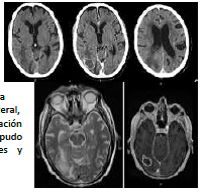

Caso 2: Hombre de 83 años afecto de Sd. de Churg Strauss en tratamiento con corticoterapia y azatioprina des de hace

4 meses. Consulta por cefalea y estado confusional de instauración brusca con fiebre. No meningismo. Se le realiza una

TC previa a la realización de PL para búsqueda de fiebre de origen desconocido (FOD) y estado confusional.

- TC craneal (5/11/2011): lesión única de 32 mm en lóbulo occipital

derecho, con edema perilesional. Captación en anillo después de la

administración de contraste ev. Estructuras de la línea media

centradas, no efectos masa significativos. Ocupación de ventrículo

lateral derecho por material hiperdenso. No hidrocefalia.

- RM (10/11/2011): se sospecha etiología TBC. Se hace la RM para mejor

estudio (lo recomienda el TC). Se observa pus en la cisterna

interpeduncular. Ventriculitis por absceso abierto a ventrículo ipsilateral,

con nivel, y también al cuerno postoccipital izquierdo. Probable afectación

del espacio subaracnoideo (leptomeningitis purulenta), aunque no se pudo

demostrar captación meníngea (por tratamiento con corticoides y

antibiótico)